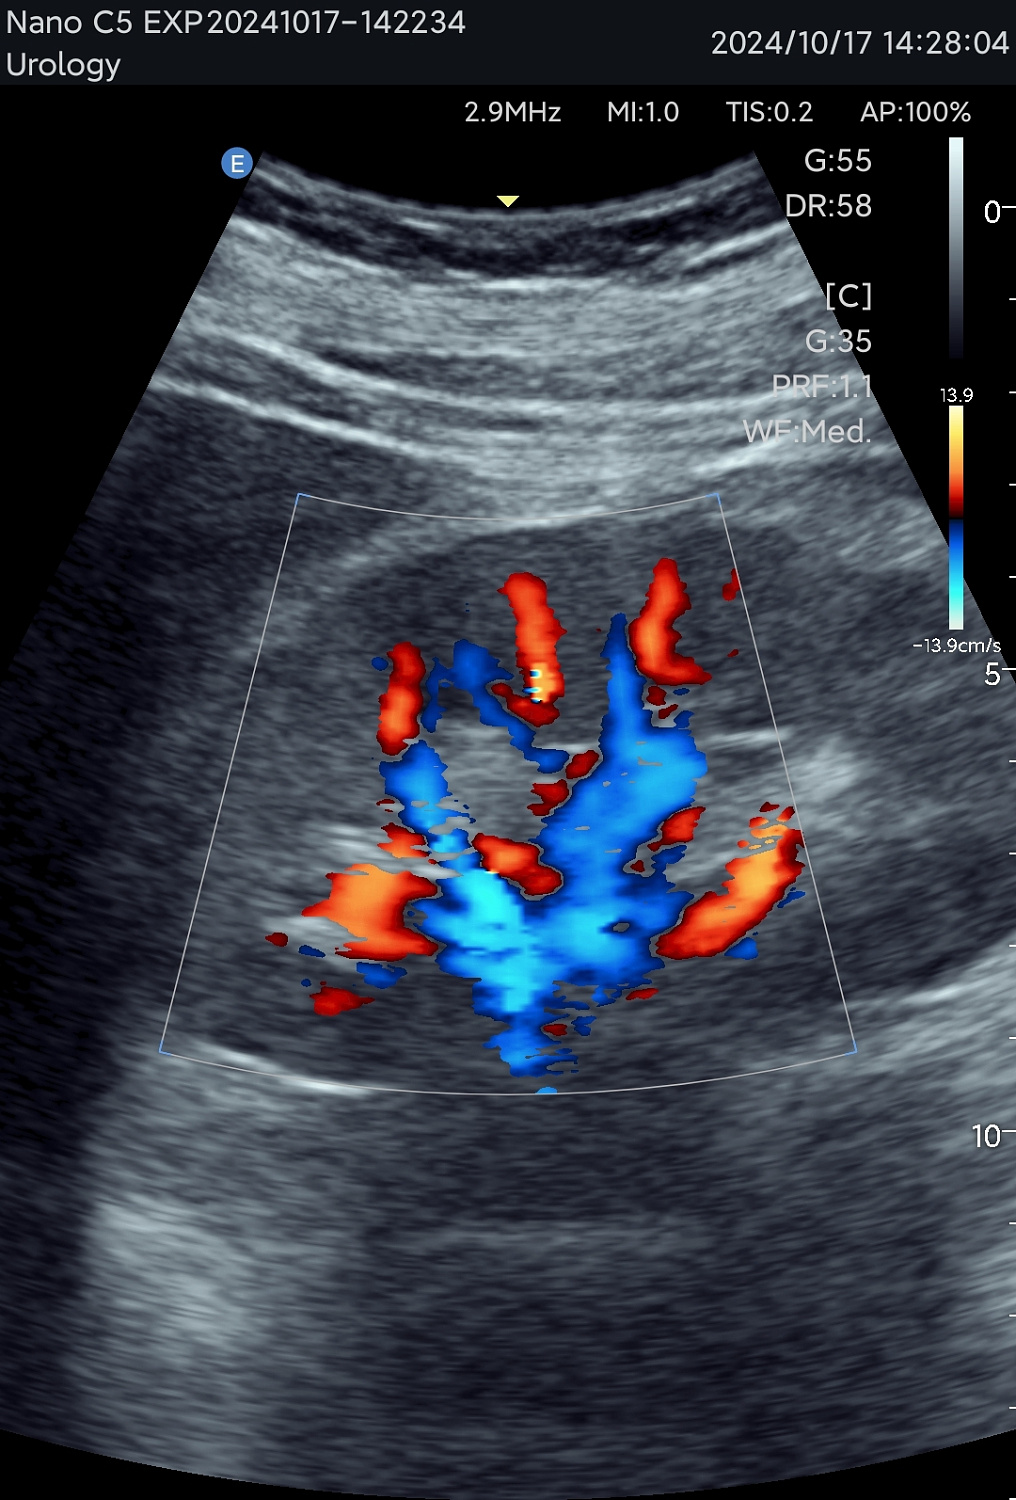

Технология зональной сонографии — это совершенно новый подход к получению и обработке ультразвуковых изображений. EDAN SynSight может использовать всю информацию, содержащуюся в наборе эхо-данных, полученных в каждой большой зоне, и таким образом охватывать поле зрения за меньшее количество циклов передачи/приёма. Исходная необработанная эхо-информация многократно обрабатывается в процессоре канальной области для формирования оптимальных изображений.

Новый стандарт портативного УЗИ

Используйте перспективную технологию визуализации в портативном УЗ-сканере. Интерфейс устройства интуитивно понятен, а применение современных режимов сканирования обеспечивает эффективную и точную диагностику в различных клинических ситуациях. Аппарат оптимален как для работы в клинике, так и для неотложной помощи, повышая качество обследования у постели больного.